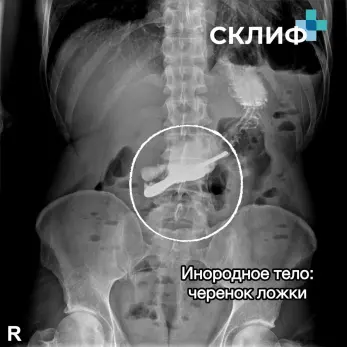

В списке - беспроводные наушники, которые отправились в «путешествие» по пищеварительному тракту. Гвозди - мастера, пытавшиеся удержать их зубами во время ремонта, столкнулись с кошмарной реальностью. Свиное ребро, абрикосовые косточки, кусок мяса и даже черенок ложки - напоминание о том, что спешка за столом может обернуться трагедией. А также зубные коронки и различные украшения.

фото: Склиф